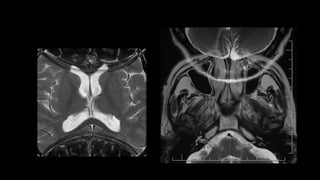

También conocido como envolvente , es un artefacto

de MRI que se encuentra con frecuencia cuando el

campo de visión (FOV) es más pequeño que la parte

del cuerpo que se está fotografiando. La parte del

cuerpo que se encuentra más allá del borde del FOV se

proyecta en el otro lado de la imagen.